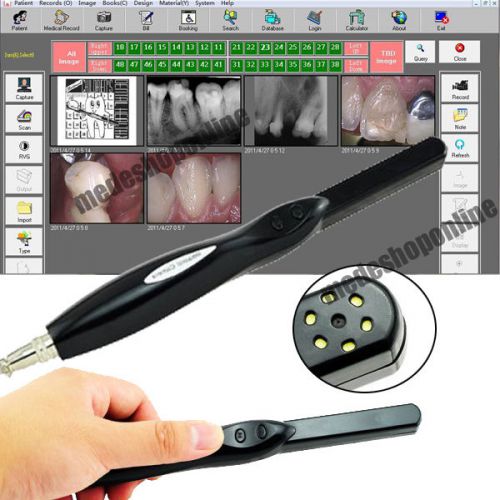

Brand | Denshine |

| Picture | 6.0M pixel CMOS | ||

| Model | OC-7 | ||

| Scope of focus | 10-50mm | ||

| Compatible with | Windows XP /Windows Vista/Windows 7 | ||

| Power supply | power through USB cable | ||

| Power | 10-50mm | ||

| Lamp | 6pcs Ultra Bright LED | ||

Dental Dentist HD USB 2.0 Intra Oral Camera 6 Mega Pixels 6-LED With Software

2pcs Dental Intra Oral Camera Intraoral Mega Pixels Digital USB Imaging System

Dental USB Otoscope Endoscope Microscope Intra Oral CAMERA PEN Video Function

Dental USB Otoscope Endoscope Microscope Intra Oral DIGITAL PEN CAMERA Y002

2015 CECMOS CCD Dynamic 4 Mega Pixels Dental Intraoral Intra Oral CameraWattenty

1/4Sony HAD CCD Dental Intraoral oral Camera 4 Mega Pixels 6 LED VGA SoftwareA++

NEW Dynamic 4 Mega Pixels 6-LED Dental Intraoral Intra Oral Camera USB 2.0 ca

2016 Version Dynamic 4 Mega Pixels Dental Intraoral Intra Oral Camera USB 2.0